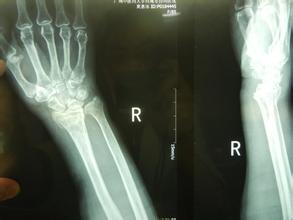

桡骨是人体前臂双骨之一,位于前臂外侧,大拇指一侧,分为一体和两端。是前臂长骨之一;蛙、蟾蜍等动物的桡骨与尺骨愈合成桡尺骨。骨密度仪厂家山东国康为您讲述桡骨引起的桡骨远端骨折。

桡骨远端骨折非常常见,都有哪些原因引起的呢?

1、跌倒后腕关节处于背伸,手掌着地,重力集中于桡骨远端松质骨处而引起骨折。老年人由于骨质疏松,轻微外力即可造成骨折,大多数是粉碎骨折。这是最常见的一种桡骨远端骨折的原因。

2、跌倒后手背着地,骨折远端向掌侧及尺侧移位。这种情况比较少见。

3、跌倒后手掌或手背着地,重力向上传递后近排腕骨撞击引起桡骨关节面骨折,桡骨下端掌侧或背侧形成关节面软骨的骨折块,骨块常向近侧移位,引起腕关节脱位。青壮年发生几率高。

桡骨远端骨折应及时去正规医院就医,根据骨折的严重性合理的治疗。骨折治疗期间患者要注意肩、肘及手指的活动锻炼,锻炼要适量。尤其老年人通过锻炼预防肩关节僵硬。同时还要注意桡骨远端骨折的并发症。部分患者愈合较好,而损伤较重患者或者治疗不当容易引起骨骺早期闭合者,长期不矫正就可出现尺骨长、桡骨短,手腕桡偏的曼德隆样畸形。此并发症给患者身心带来痛苦,因此应及时矫正和处理。